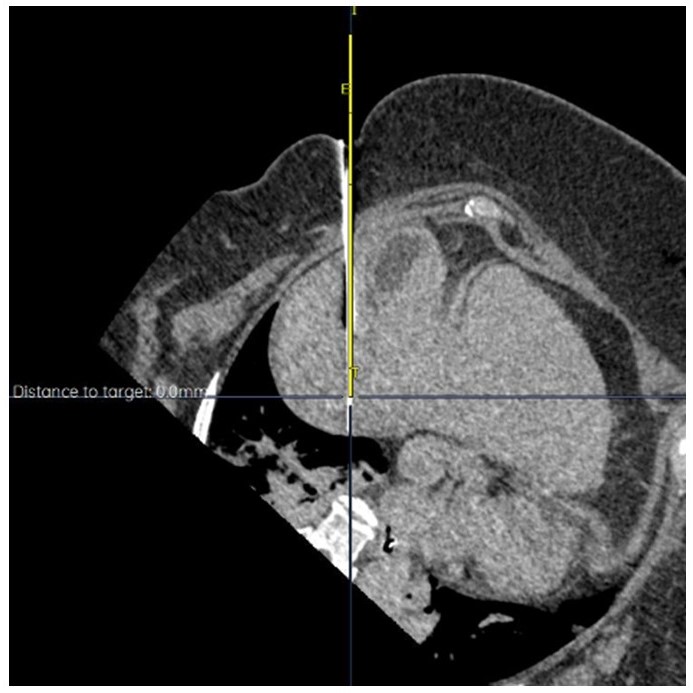

Dr. Berman’s academic and clinical career is distinguished by a strong commitment to innovation in minimally invasive cancer therapy. He has played pivotal roles in numerous clinical trials investigating emerging locoregional and immuno-oncology strategies, including investigator positions in the CapTemY90 trial and other advanced-phase studies for neuroendocrine tumors, HCC, and pancreatic cancer. He has authored over 30 peer-reviewed publications and book chapters, including work on Y-90 dosimetry, intraoperative embolization, and imaging response assessment, and has been recognized with honors such as “Top Doctor” in San Diego Magazine and the UCSD Resident Teaching Award.